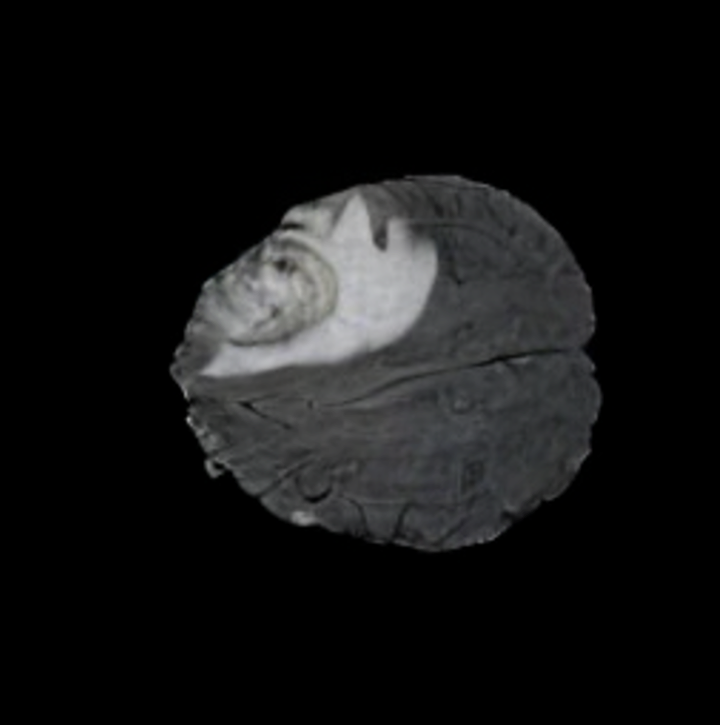

Notably, X-Diffusion achieves sota dB for a few input slices while baselines require more than 60 input slices to achieve similar performance (Figure 7). The margin is more than 12 dB PSNR for the 1-slice input in both the BRATS and the UK Biobank benchmarks (see Table 1 and Figure 6). For reference, two randomly sampled MRIs from the UK Biobank would have a PSNR of 15.95 dB 0.36 (on 4800 randomly sampled examples). The slices from 3D reconstructed volumes at varying depths and axis of rotation visually match the ground truths (see Figures 5 and Figure 4). We also plot the error map (Figure 4) of such X-Diffusion generations to highlight the differences with the ground truth MRIs.

Tumour Information Preservation. For the brain tumor segmentation, we use a Swin UNETR model[27, 70], trained with random rotation, and intensity as data augmentation. In Figure 5, we highlight the tumor profiles of the generated MRIs compared to the ground truth tumour profile. In the test set with human ground-truth annotations (), the real MRI Dice score is 85.15 while the generated MRIs from a single slice have a dice score of 83.09. This shows how the generated MRIs indeed preserve the tumor information and can act as an affordable and informative pseudo-MRI, before conducting an actual costly MRI examination in hospitals.